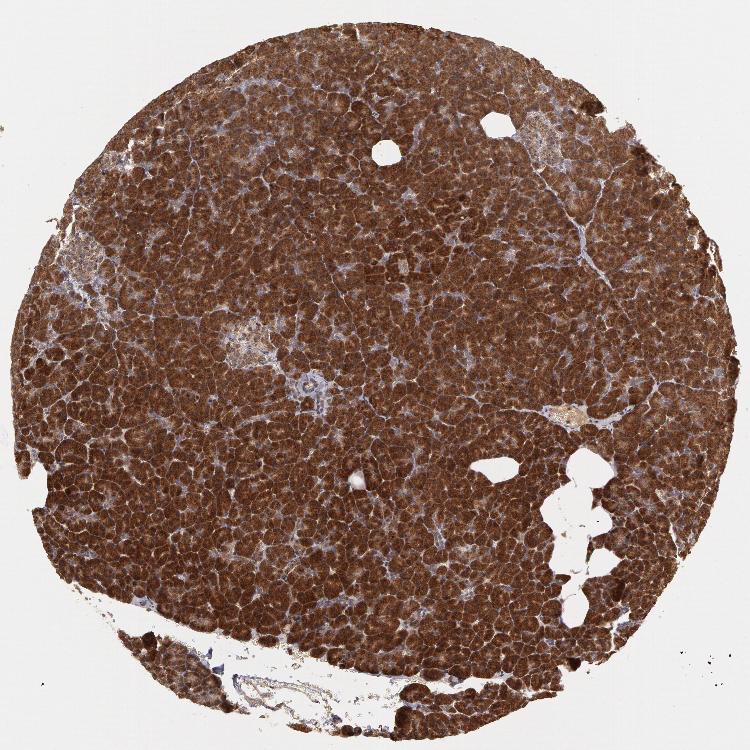

PANCREAS - Antibody stainingi

Antibody staining in the annotated cell types in the current human tissue is reported as not detected, low, medium, or high, based on conventional immunohistochemistry profiling in selected tissues. This score is based on the combination of the staining intensity and fraction of stained cells.

Each image is clickable and will lead to virtual microscopy that enables deeper exploration of all samples and also displays staining intensity scores, fraction scores and subcellular localization as well as patient and tissue information for each sample.

Antibody HPA001358

Exocrine glandular cells High

Pancreatic endocrine cells Low